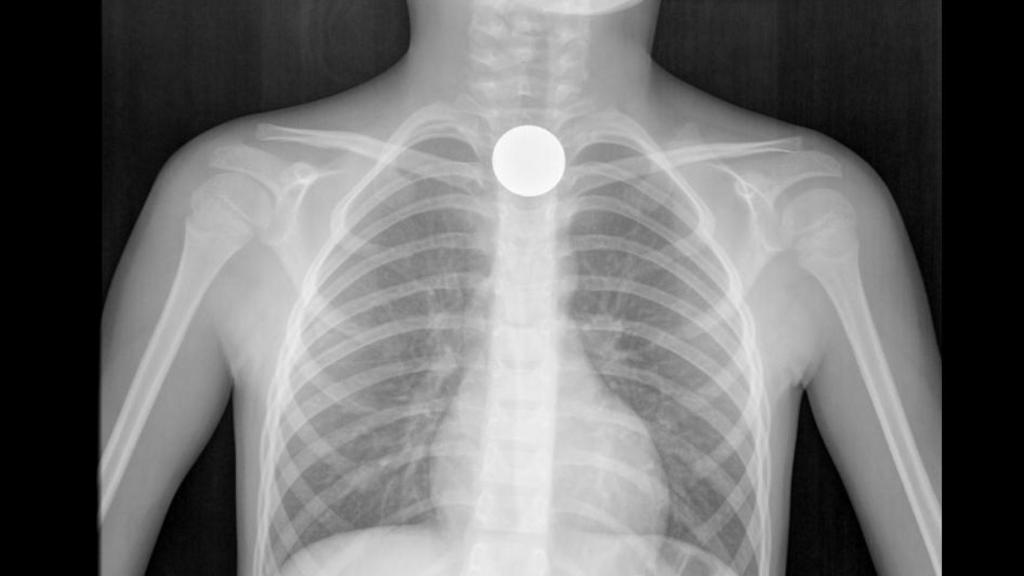

Radiografía que muestra el atragantamiento de un niño causado por una moneda.

Los alimentos no son los únicos responsables de los atragantamientos. Los juguetes, sobre todo si tienen piezas pequeñas, son sospechosos habituales en los niños. Los adultos tampoco se libran: "Un botón, el tapón de un rotulador o un bolígrafo... No es extraño".